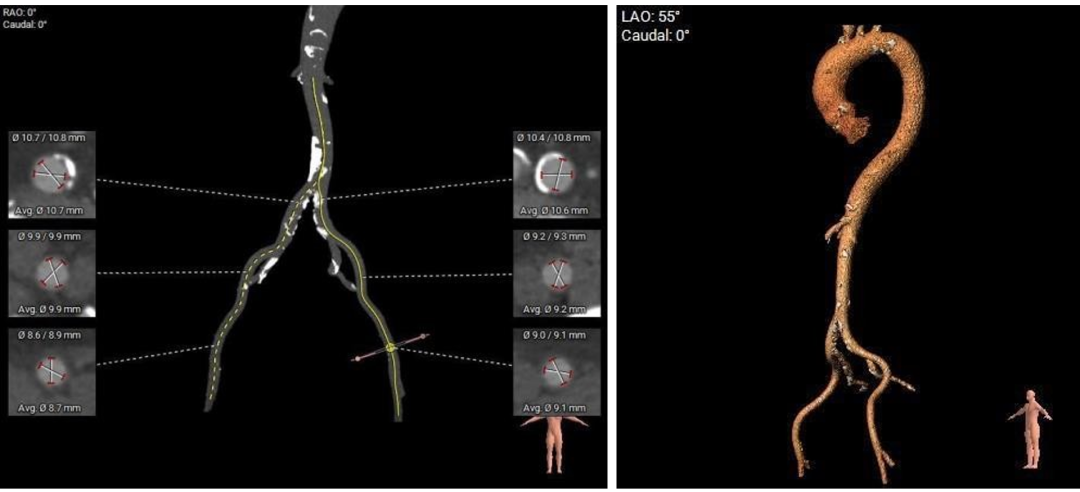

主动脉根部测量:

主动脉弓测量:

主动脉弓部宽度、角度可。

•双侧股-腹主动脉走形适宜,内径可,腹主-髂总动脉大量斑块钙化分布。